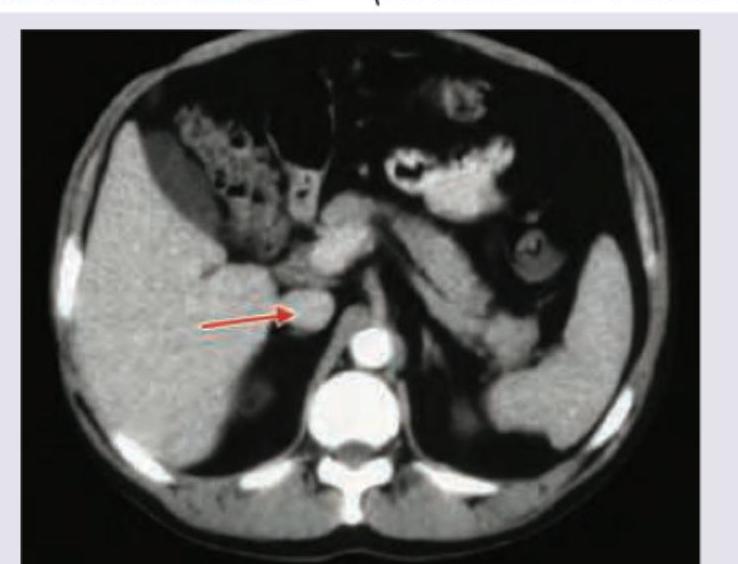

The following CT abdomen shows:

Explanation: ***Portal vein*** - The arrow points to a vessel receiving blood from the splenic and superior mesenteric veins, which is characteristic of the **portal vein** entering the **liver parenchyma**. - The portal vein is typically seen anterior to the **inferior vena cava** and posterior to the **common hepatic artery** at this level. *Inferior vena cava* - The **inferior vena cava (IVC)** is a large, retroperitoneal vessel located posterior to the liver and to the right of the aorta. - The structure indicated by the arrow is clearly within the liver substance, not in the typical position of the IVC. *Splenic vein* - The **splenic vein** runs horizontally behind the body of the pancreas and joins with the superior mesenteric vein to form the portal vein. - The vessel shown is within the liver, distal to the formation of the portal vein. *Superior mesenteric vein* - The **superior mesenteric vein (SMV)** typically runs vertically in the mesentery and joins the splenic vein to form the portal vein. - The indicated structure is within the liver hilum, not in the anatomical location of the SMV.